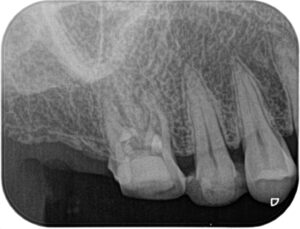

術前:一見根管治療は十分にされているように思えますが、近心根に破折器具および小さな根尖病変を認めます。